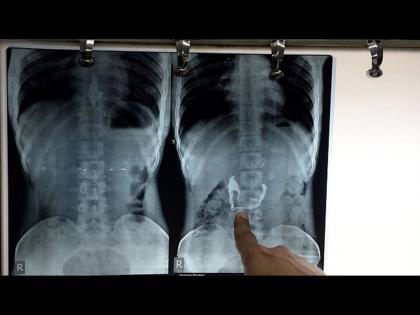

पण चोरांकडे काहीच सापडलं नाही आणि उलट चोर म्हणाले की, तुमच्याकडे काय पुरावा आहे की, आम्ही सोन्याची चेन चोरी केली. काही न मिळाल्यानंतर संशयितांना टेस्ट करण्यासाठी नेण्यात आलं. त्यांचा एक्स-रे केला तर सगळे हैराण झाले.

एका चोराच्या एक्स-रेमध्ये स्पष्ट दिसत होतं की, त्याच्या पोटात सोन्याची चेन आहे. त्यांना हॉस्पिटलमध्ये नेण्यात आलं आणि त्याच्यावर उपचार सुरू आहेत.